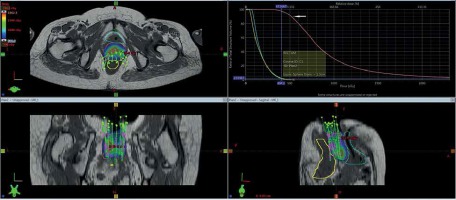

Gross tumor volume, high-risk clinical target volume (HR-CTV), intermediate-risk clinical target volume (IR-CTV), and OARs were delineated with the use of MR T2 weighted images, following GEC-ESTRO guidelines. HR-CTV delineation was challenging, as pre-brachy MR images were not available. This was overcome by changing the contrast resolution and EUA findings (Figure 1). T1 weighted images were helpful for a catheter reconstruction, and the catheters were better appreciated as black straight lines without any interruptions. Haack et al. showed that plastic catheters are well suited for MR-based reconstruction in T1 images and all catheters were visible without artifacts [9]. Depending of the extent of disease, the active lengths of the implant ranged from 6-8 cm. The dose prescribed was 20 Gy in 4 fractions (30 Gy low-dose-rate [LDR] equivalent [EQD2]) to HR-CTV, 6 hours apart, and delivered over two days. Doses of 2 cc of bladder and rectum were restricted to less than 4.0 and 3.7 Gy per fraction, respectively. With our initial experience, the dose escalation was considered to be 6 Gy per fraction. Treatment plans were performed using volumetric optimization with 5 mm dwell position (Figure 2). The OARs constraints were met using manual dragging of isodose lines. The treatment was executed using 192Ir Gammamed Plus HDR remote afterloading machine (Varian Medical Systems, Palo Alto, CA, USA), with 192Ir high activity of 10 Ci max, source of 4.6 mm active length and 0.9 mm in diameter.